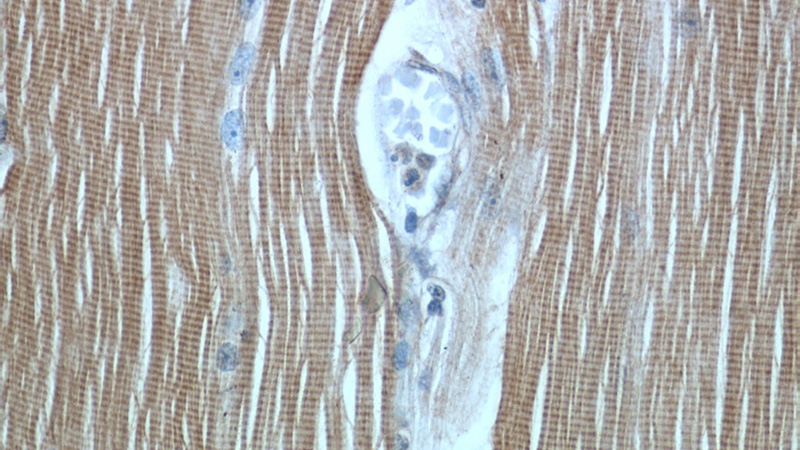

Immunohistochemical of paraffin-embedded human skeletal muscle using Catalog No:116151(TNNI1 antibody) at dilution of 1:50 (under 40x lens)